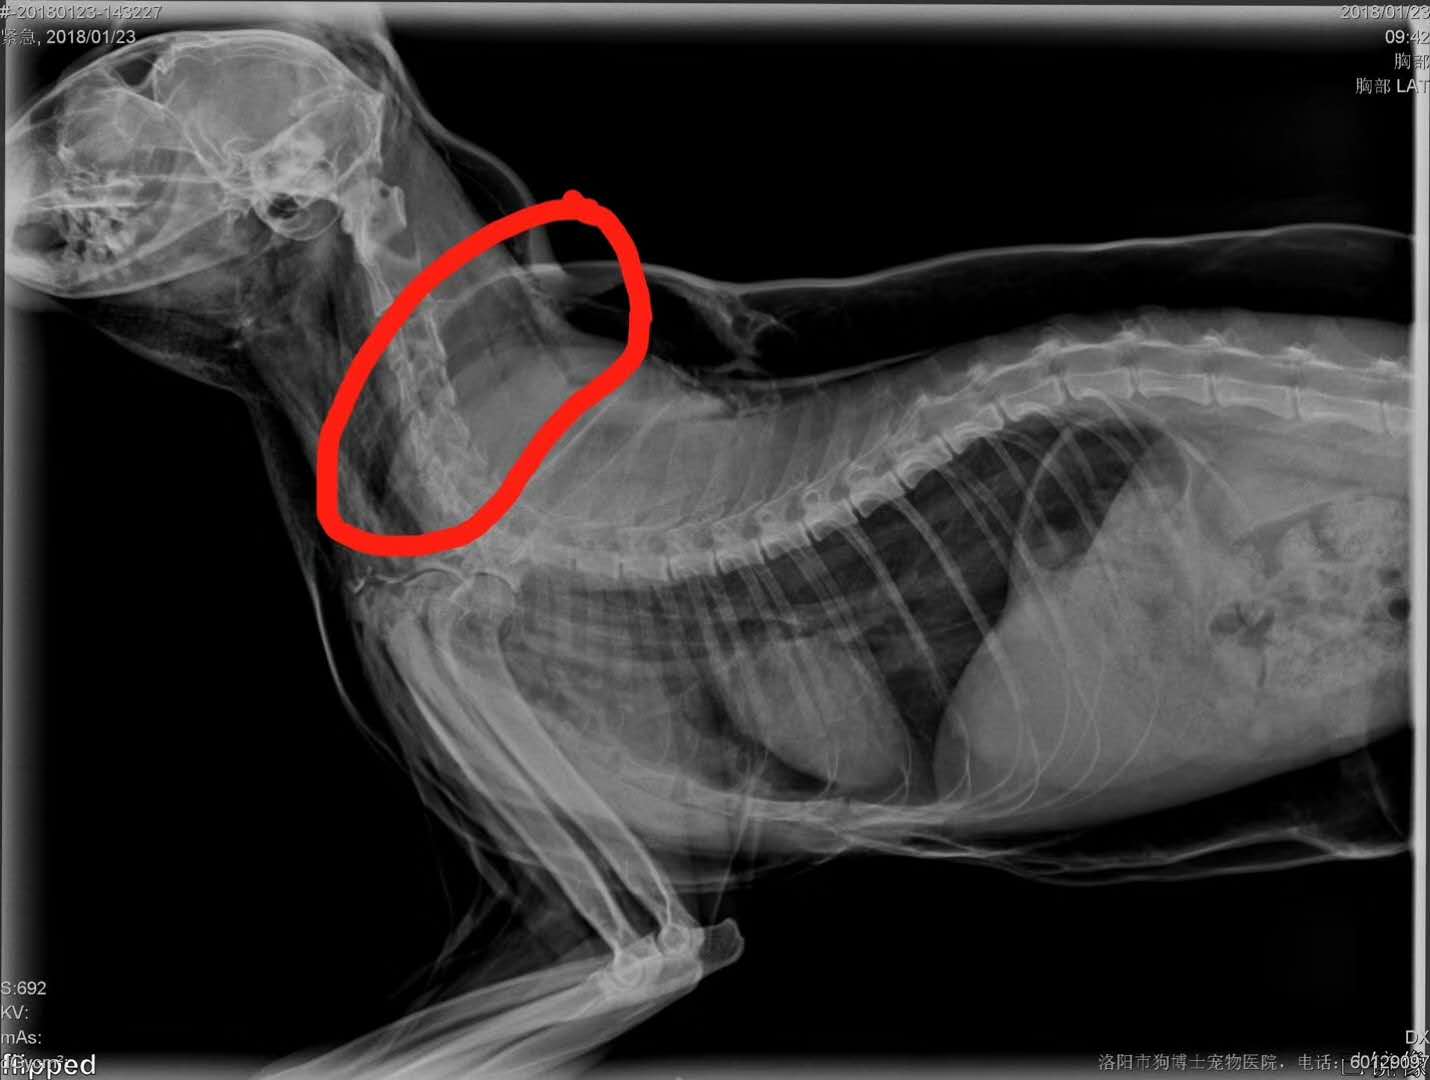

轉(zhuǎn)院全身氣腫病例治愈出院:暹羅貓,發(fā)財(cái),近期在其他醫(yī)院做的絕育手術(shù),術(shù)后出現(xiàn)全身氣腫(第2,第3張照片為原醫(yī)院拍攝),轉(zhuǎn)賬至我院,經(jīng)我院檢查發(fā)現(xiàn),在貓咪氣管入胸段,約有5.6mm大小孔洞,氣體延此孔泄露,并移行到頸部背測,接入皮下疏松結(jié)締組織,進(jìn)一步擴(kuò)散至全身。推測可能與絕育手術(shù)呼吸麻醉時(shí)氣管插管不當(dāng)有關(guān)。我院采取壓迫保守療法,住院10天,痊愈出院。PS:寵物主人選擇醫(yī)院時(shí),一定要慎重,就診時(shí)關(guān)鍵是大夫水平,其他是次要因素。